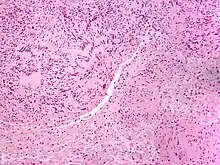

| Micrograph of a palisaded encapsulated neuroma | |

PEN is diagnosed by clinical recognition of the lesion and on subsequent histologic examination. Typically, the lesions are suspected to be schwannomas or neurofibromas clinically with PEN being an incidental finding on histology.[3]

PEN is typically diagnosed in patients between the ages of 40 and 60 years and occurs more frequently in females than males. The diagnosis of PEN may be difficult, even with confirmatory histology, due to its histological similarities with schwannomas and neurofibromas. It is imperative that the correct diagnosis is made the misdiagnosis of a neurofibroma may lead to unnecessary further investigation into associated systemic syndromes such as neurofibromatosis type 1 or multiple endocrine neoplasia syndrome.[3][4]